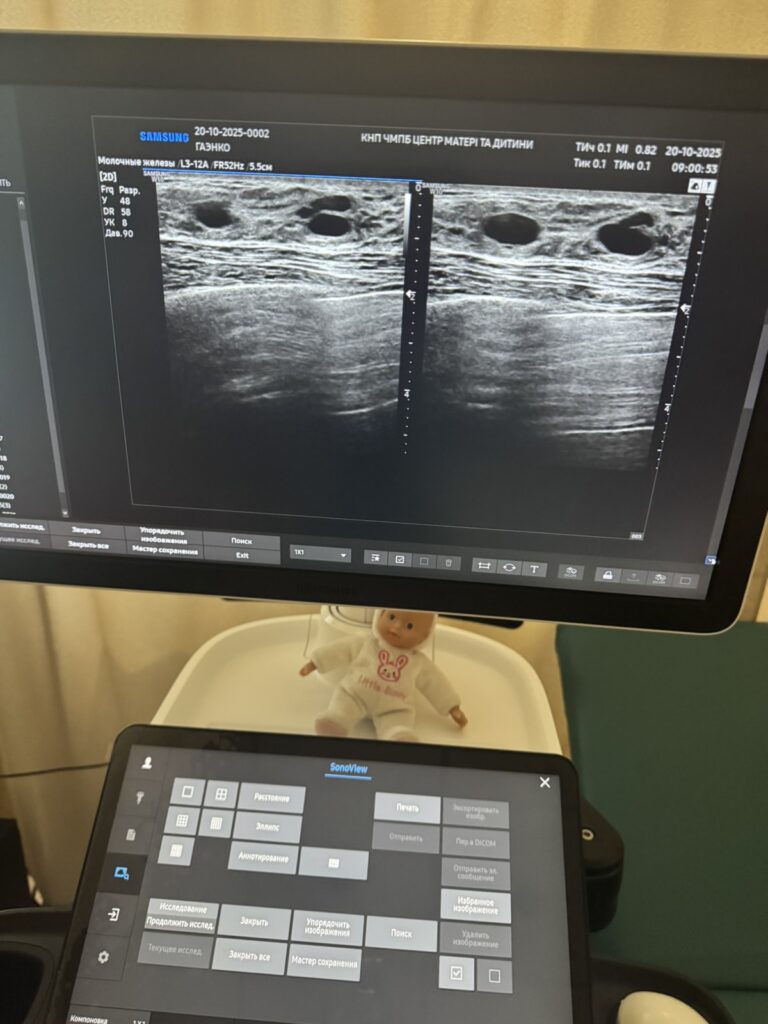

• УЗД молочних залоз — жінкам до 40 років або як доповнення;

до 40 років потрібно 1 раз на рік або за показаннями проводити УЗД молочних залоз;

В КНП Черкаський міський пологовий будинок “Центр матері та дитини” ви маєте змогу пройти мамографію безкоштовно за програмою медичних гарантій, за умови наявності електронного направлення від сімейного лікаря чи акушера-гінеколога, а також пройти ультразвукове дослідження молочних залоз. В нашому закладі зазвичай проводиться 10 -12 мамографій щодня , та 2-5 ультразвукових обстежень молочних залоз.